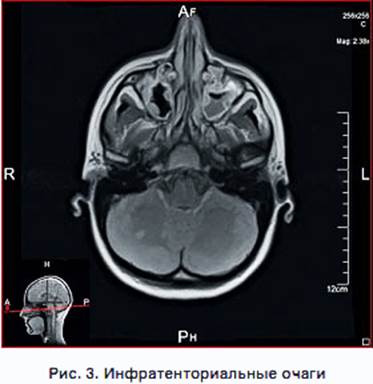

· инфратенториальные очаги (расположены ниже намета мозжечка) – часто локализуются в ножках мозжечка; очаги в мосту нередко прилежат к четвертому желудочку; к ним приравниваются очаги в спинном мозге;